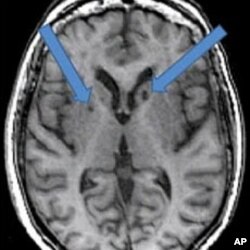

In this scan of a patient who has had two strokes, the arrows point to dark holes filled with fluid. Neuropsychologist Adam Brickman at the Columbia University School of Medicine, says these dark spots were once healthy cells killed by blood clots traveling to the brain.

But scientists have found that a silent stroke, with no obvious symptoms, is often not diagnosed or treated as quickly. The patient continues daily routines, unaware that something has happened inside the brain. The damage is detected only when the patient undergoes a special MRI imaging procedure.